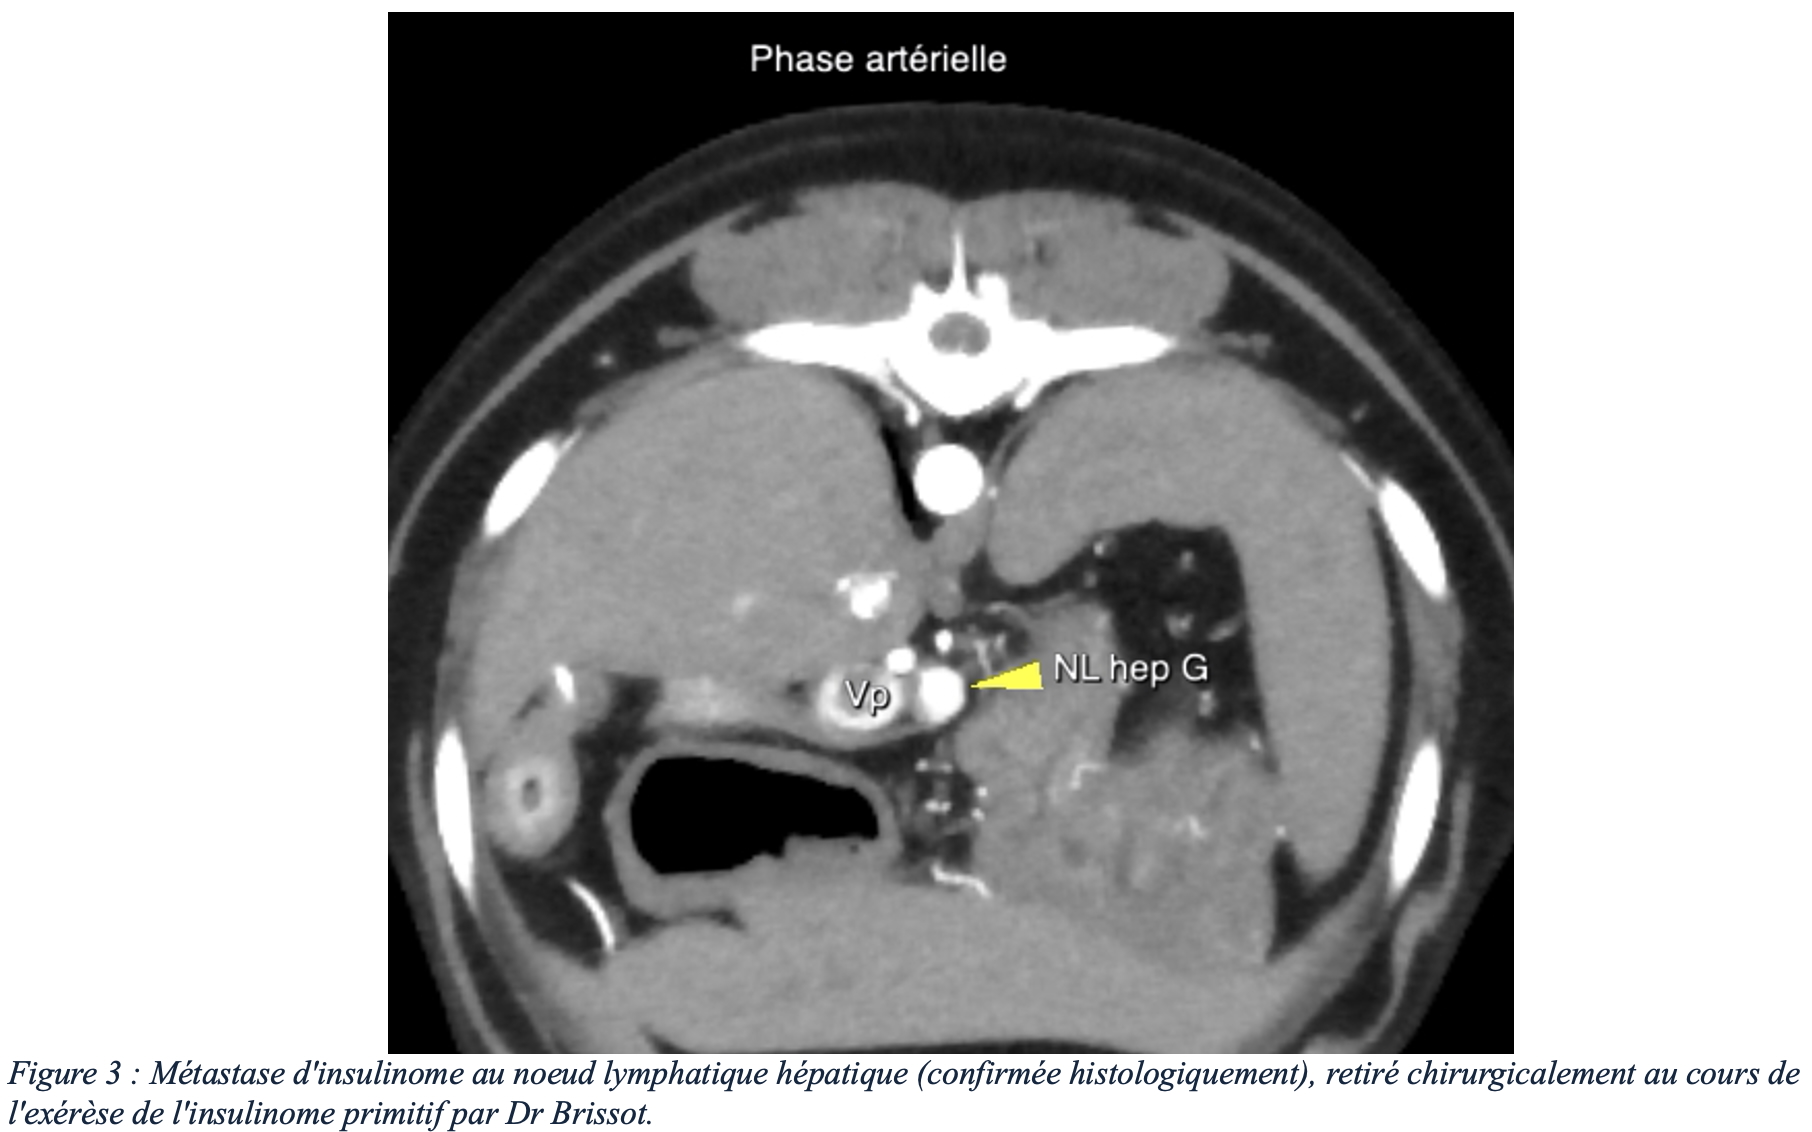

En tant que tumeur neuroendocrine, l’insulinome est quasiment systématiquement une tumeur maligne avec possibilité de dissémination métastatique. Les sites de métastases les plus fréquents sont les nœuds lymphatiques de drainage (notamment hépatiques, spléniques et coliques) et le foie. La présence de métastase est le seul critère pronostic négatif mis en évidence.

Le scanner, et plus particulièrement la phase artérielle tardive d’un angioscanner (3) (figure 2), est un examen présentant une sensibilité nettement supérieure à l’échographie (4). En effet, les insulinomes et leurs métastases présentent un rehaussement intense et précoce après injection intraveineuse de contraste iodé, permettant une détection plus fiable des insulinomes et leurs éventuelles métastases (bien que des faux positifs soient possibles), tout en s’affranchissant des limites liées au gabarit de l’animal (figures 3 et 4). Les angioscanners peuvent être effectués manuellement, mais les injecteurs automatiques de contraste facilitent la partie technique de cet examen (figure 5).